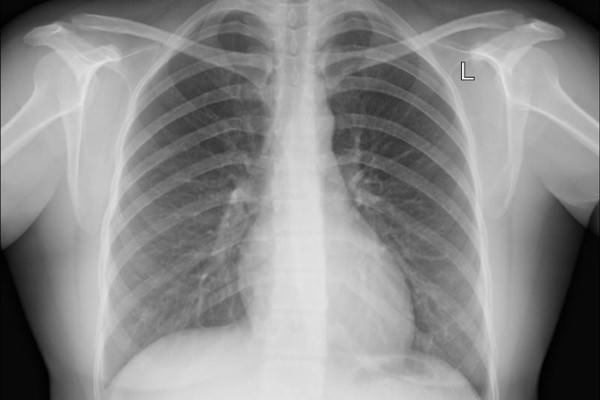

Основной целью флюорографии, которую все должны обязательно проходить 1 раз в год, является профилактика и выявление различных патологий и заболеваний на стадии их зарождения.

Результаты обследования дают возможность оценить состояние органов и при наличии изменений провести более детальную диагностику и назначить лечение.

С помощью флюорографии можно выявить не только типичный для людей с никотиновой зависимостью бронхит курильщика. При этом патологии органов дыхания могут развиваться и по другим причинам.

Возвращаясь к вопросу, можно ли курить перед флюорографией, надо сказать, что выкуренная сигарета за 30 минут или за час до проведения манипуляции, особо на результат не влияет. То есть при наличии патологии она в любом случае будет отражаться на снимке. А учитывая быстроту проведения исследования на флюорографическом аппарате, попавший в организм пациента табачный дым, не осложняет его поведение и не препятствует получению достоверных данных.